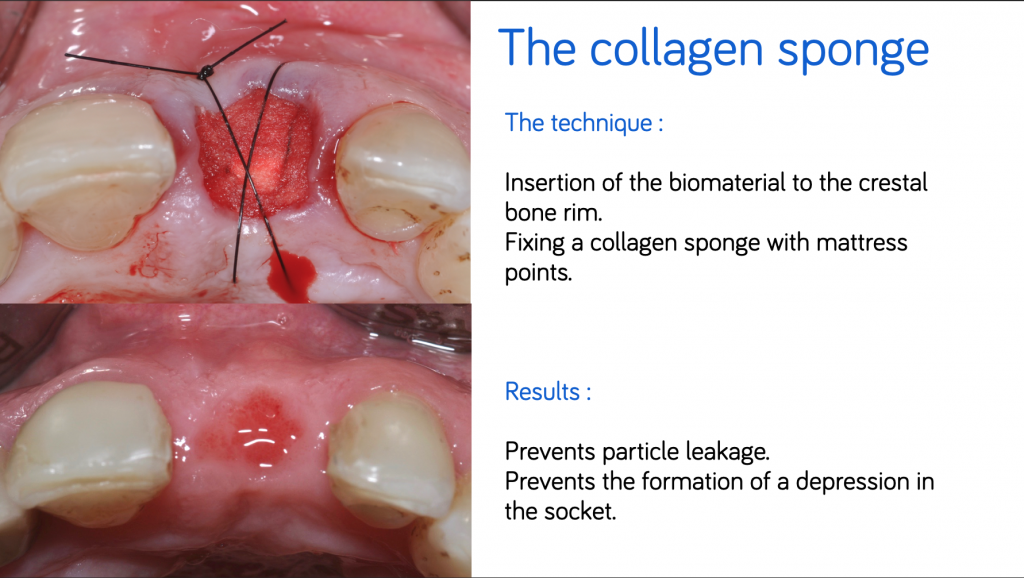

#2. The collagen sponge

Collagen sponge or "Bio-Col" technique (Sclar, 1999) consists of the insertion of a bone filling material to the crestal rim and the closure of the socket by a collagen sponge fixed by padding points.

Collagen prevents the infiltration of connective cells into the coronal portion of the socket and guides healing to prevent the formation of depression into the socket.